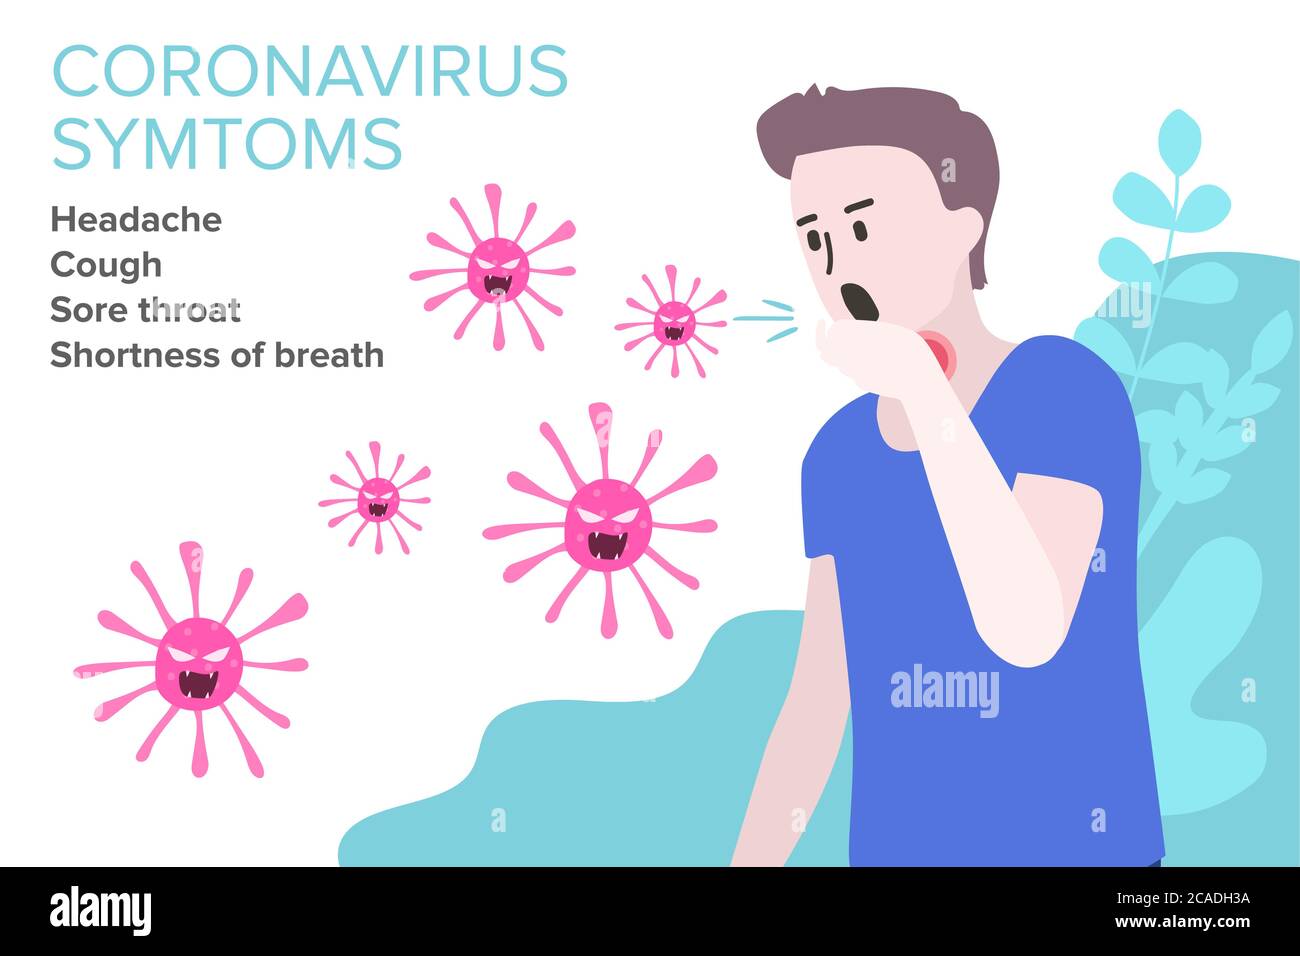

RF2CADFNB–Segno infografica con Cartoon ha tosse, febbre, Gola irritata e freddo in Coronavirus o Covid-19 focolaio.

RF2CADJ2A–Segno infografica con Cartoon ha tosse, febbre, Gola irritata e freddo in Coronavirus o Covid-19 focolaio.